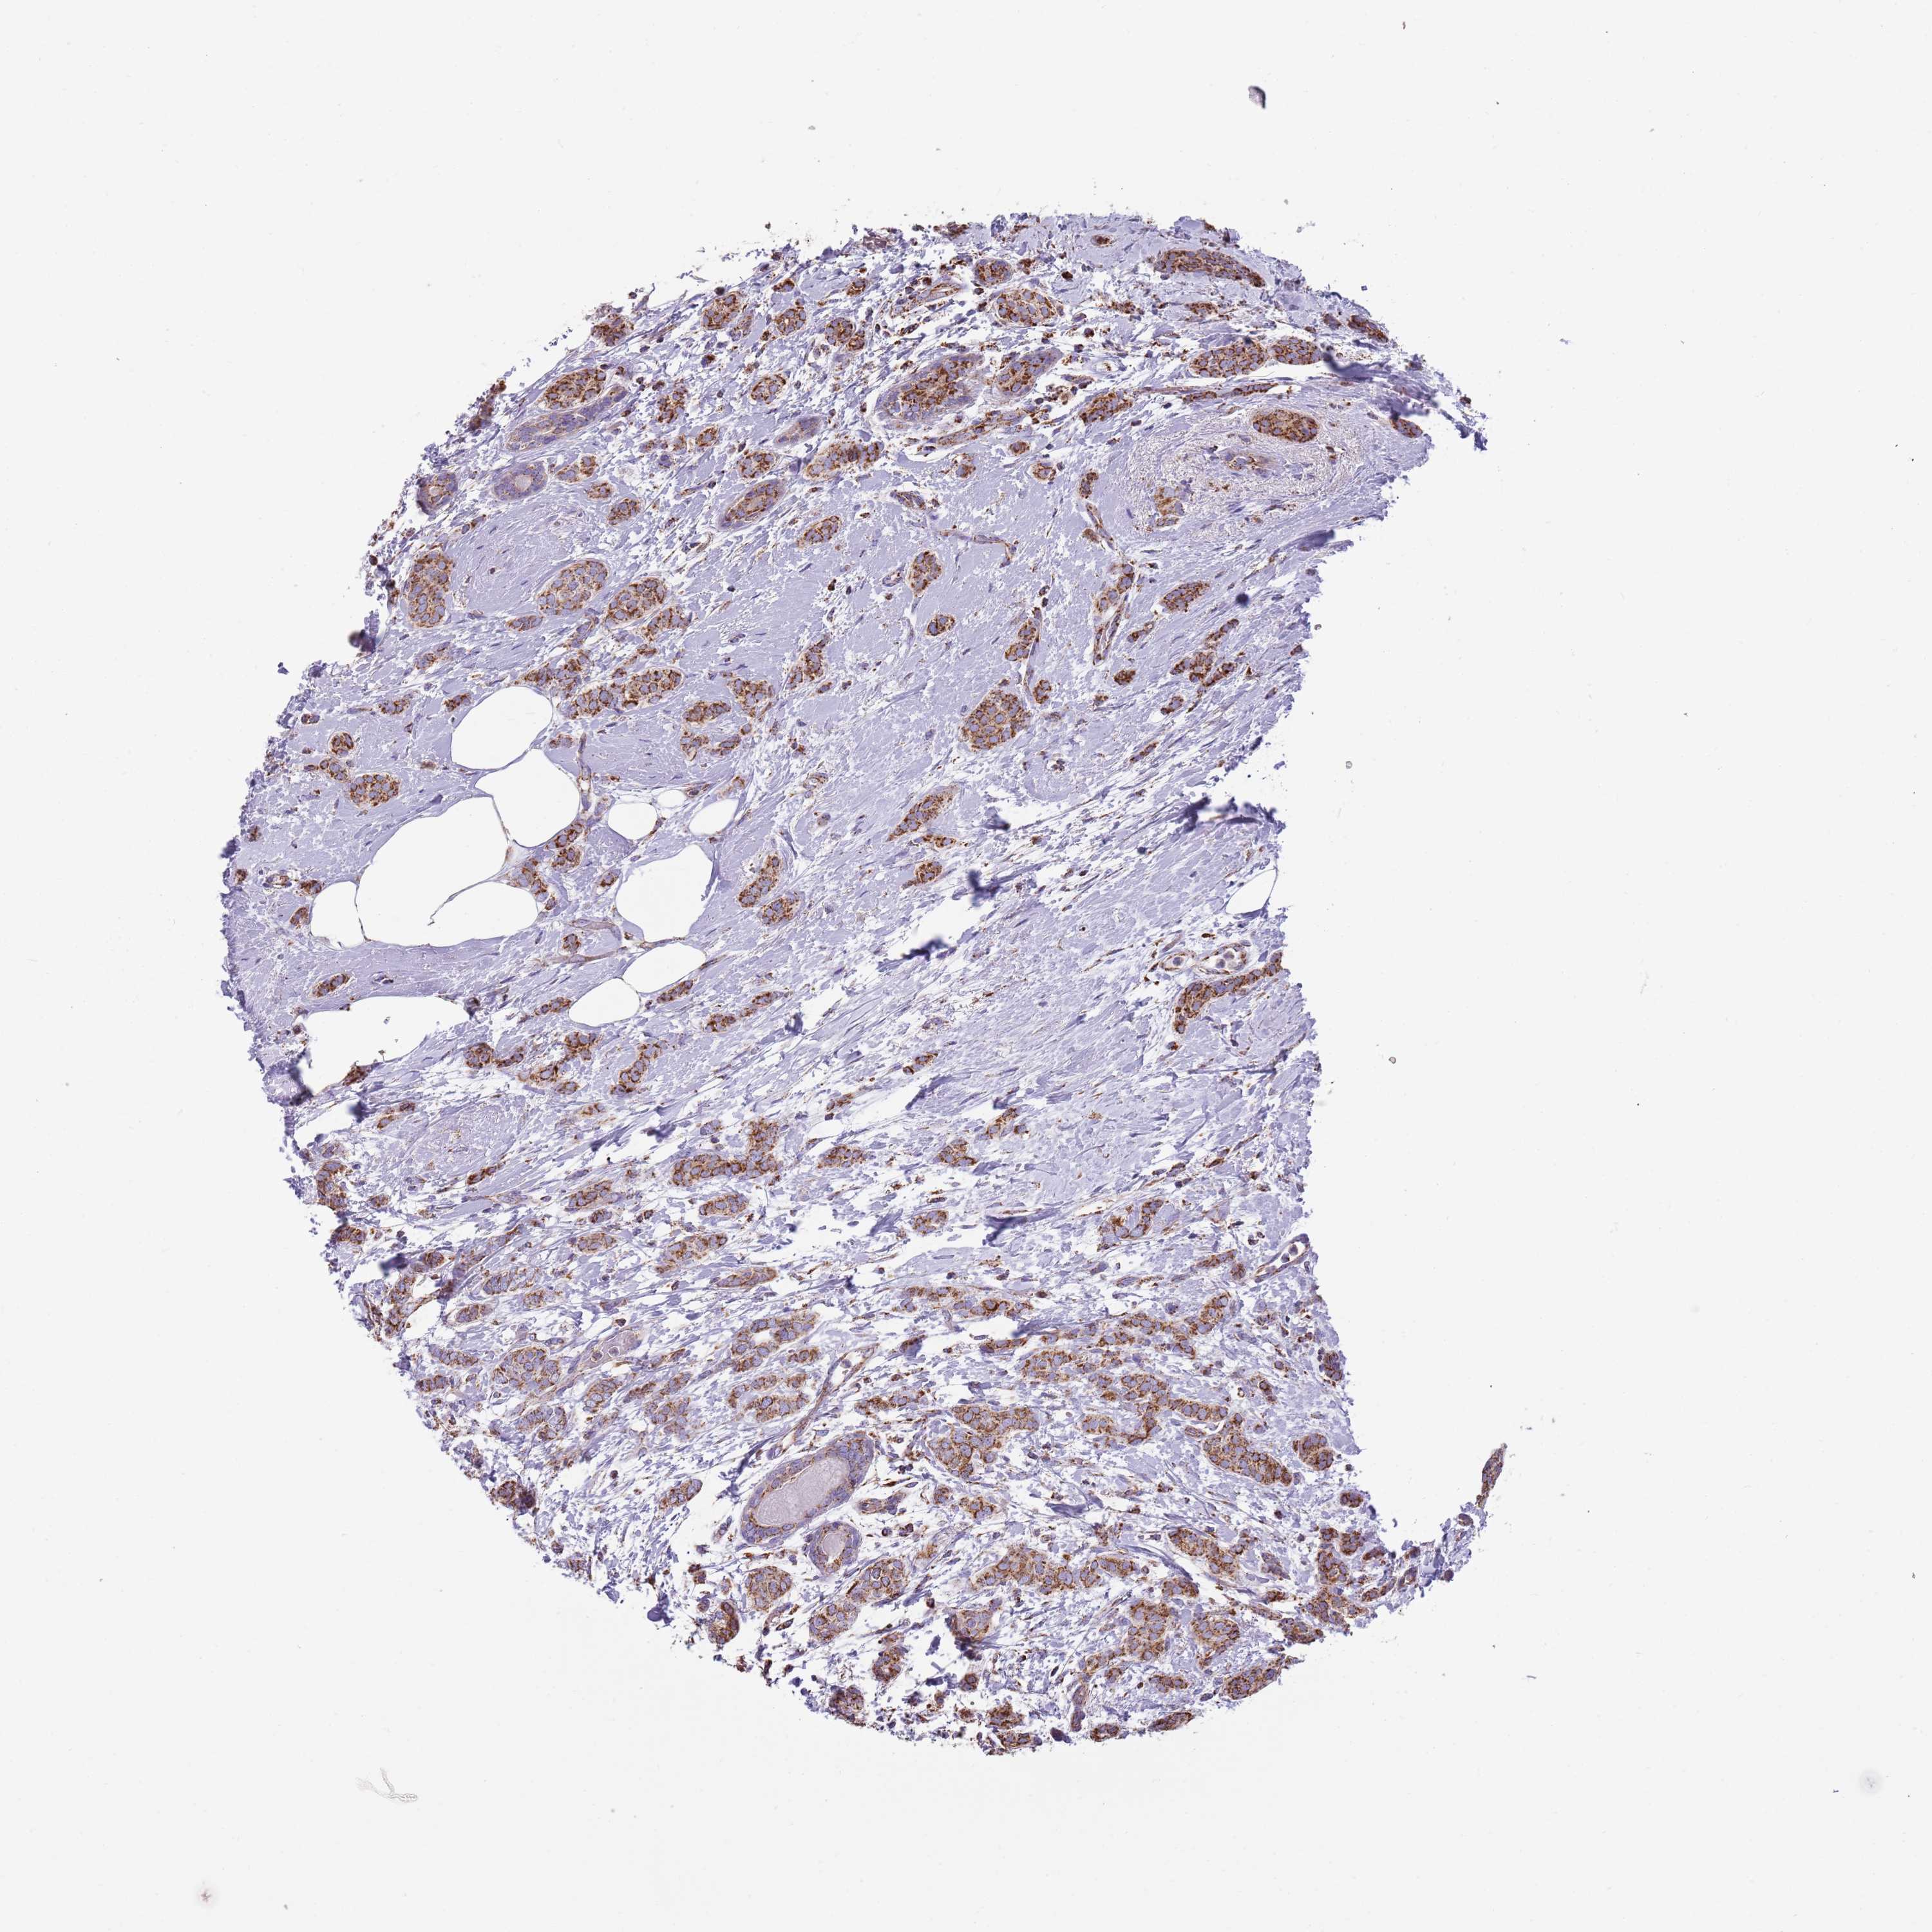

CANCER BREAST CANCER Show tissue menu

BRCA TCGA BRCA VALIDATION PROTEIN EXPRESSION